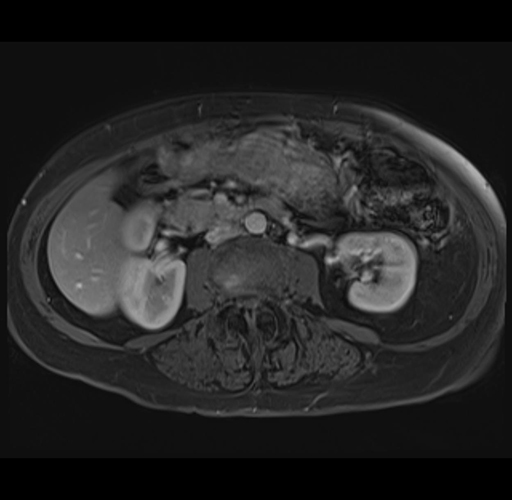

MRI T1